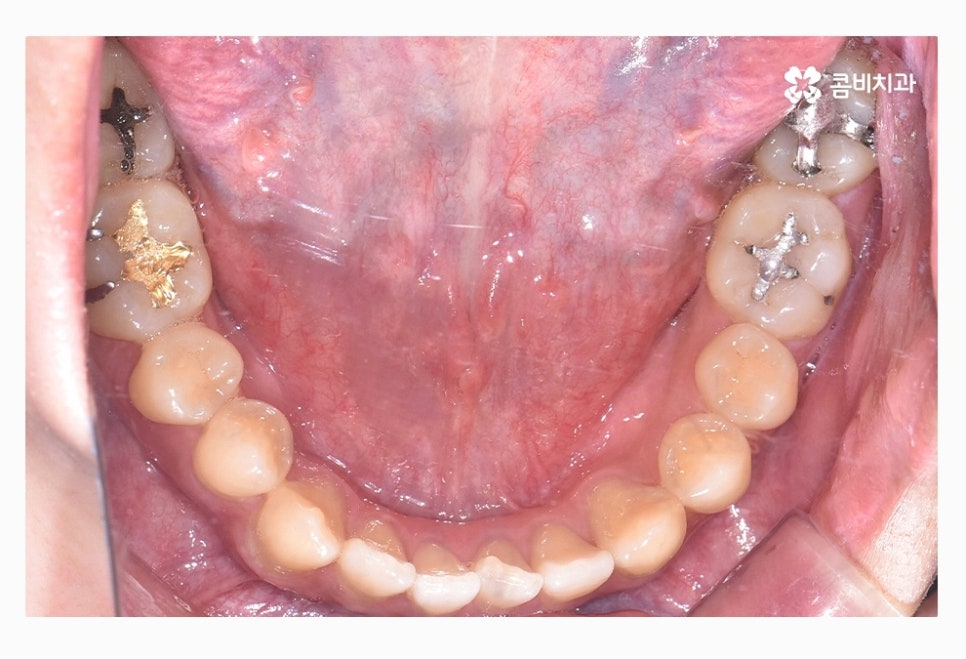

좌측 사진이 윗니이며 우측 사진이 아랫니인데

윗니가 치열이 좀 더 삐뚤다는 것을 알 수 있어요.